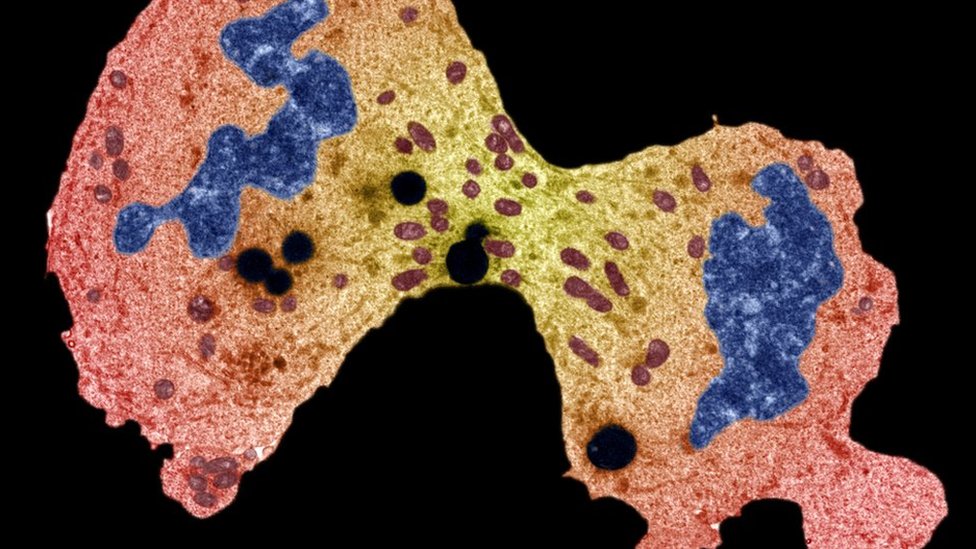

Glavni cilj terapije jeste da „ojača imuni sistem kako bi naše odbrambene ćelije mogle da otkriju i eliminišu maligne, podle ćelije raka“, objašnjava doktorka Jovanović.

Imuni sistem ljudskog organizma je podešen tako da prepoznaje strane ćelije.

Te ćelije mogu biti bakterije, virusi, ali i maligne ćelije tumora.

Međutim, usled kompleksne regulacije imunog sistema ove ćelije nekad mogu da prođu neopaženo našim imunim ćelijama i na taj način se nakon nastanka razmnožavaju i formiraju maligni tumor i metastaze.